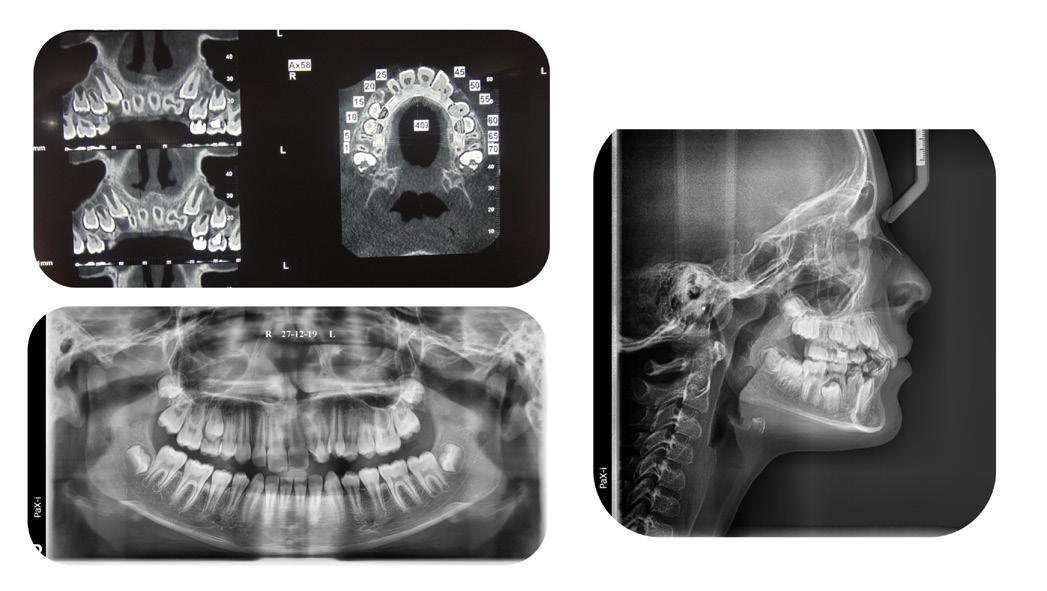

Panoramic radiogram revealed a late mixed dentition with un-erupted wisdom teeth and second molars. A significant finding was noted in that the maxillary cuspids were in transposition with the lateral incisors. There was excellent bone support and no sign of periodontal or peri-apical pathology (Figure 2-A).

Lateral Cephalometric radiogram revealed a narrow airway in the tonsil area (5.0 mm), retrognathic maxilla and mandible (SNA - 78°, SNB - 76°), retrusive maxillary incisors (U1/SN - 91°), retrusive mandibular incisors (L1/GoM - 83°). She was Class III skeletally as ANB, Wits and the Harvold ∆ were – 2.4°, -5.0 mm and 24.8 mm The patient was hyper-divergent as seen from NS/GoM of40° and a Lower gonial angle of 79.7°. The patient was in CVMS 2 - 3 (Cervical Vertebrae Maturation Stage) (Figure 2-B) and an A-P Radiogram revealed a posterior crossbite (Figure 2-C).

Figure 2A: Pre-treatment, Panoramic radiogram Figure 2B: Pre-treatment, lateral Cephalometric radiogram

Figure 2C: Pre-treatment, AP Cephalometric radiogram